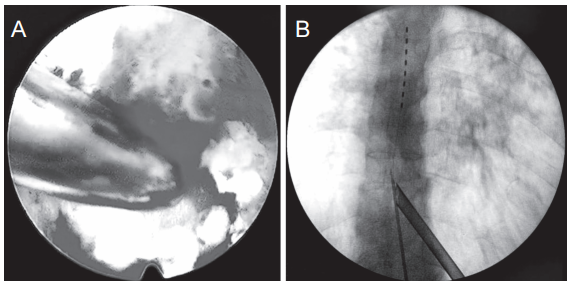

图5 脊柱内镜下硬膜外穿刺针最终位置,C 形臂下 CL最终植入位置及脊柱内镜套管位置

(A) 脊柱内镜下可见硬膜囊、硬膜外脂肪及硬膜外穿刺针;(B) C 形臂下 CL 最终植入位置及脊柱内镜套管位置